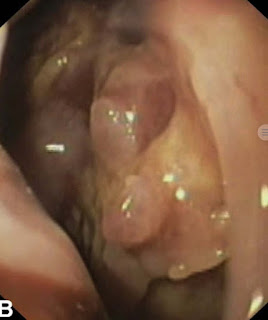

Three days later he developed 3 bouts of melaena, with a drop in hemoglobin to 7.0 gm/dL.He was resuscitated and a second CECT was performed, which revealed a bulky pancreas with multiple hypodense areas of necrosis and marked peripancreatic inflammation extending onto the posterior wall of the stomach, greater omentum, gastrocolic and gastrosplenic ligaments, root of mesentery, and left paracolic gutter (Fig.1).

![]() |

| Fig 1 CT scan abdomen showing severe pancreatitis |